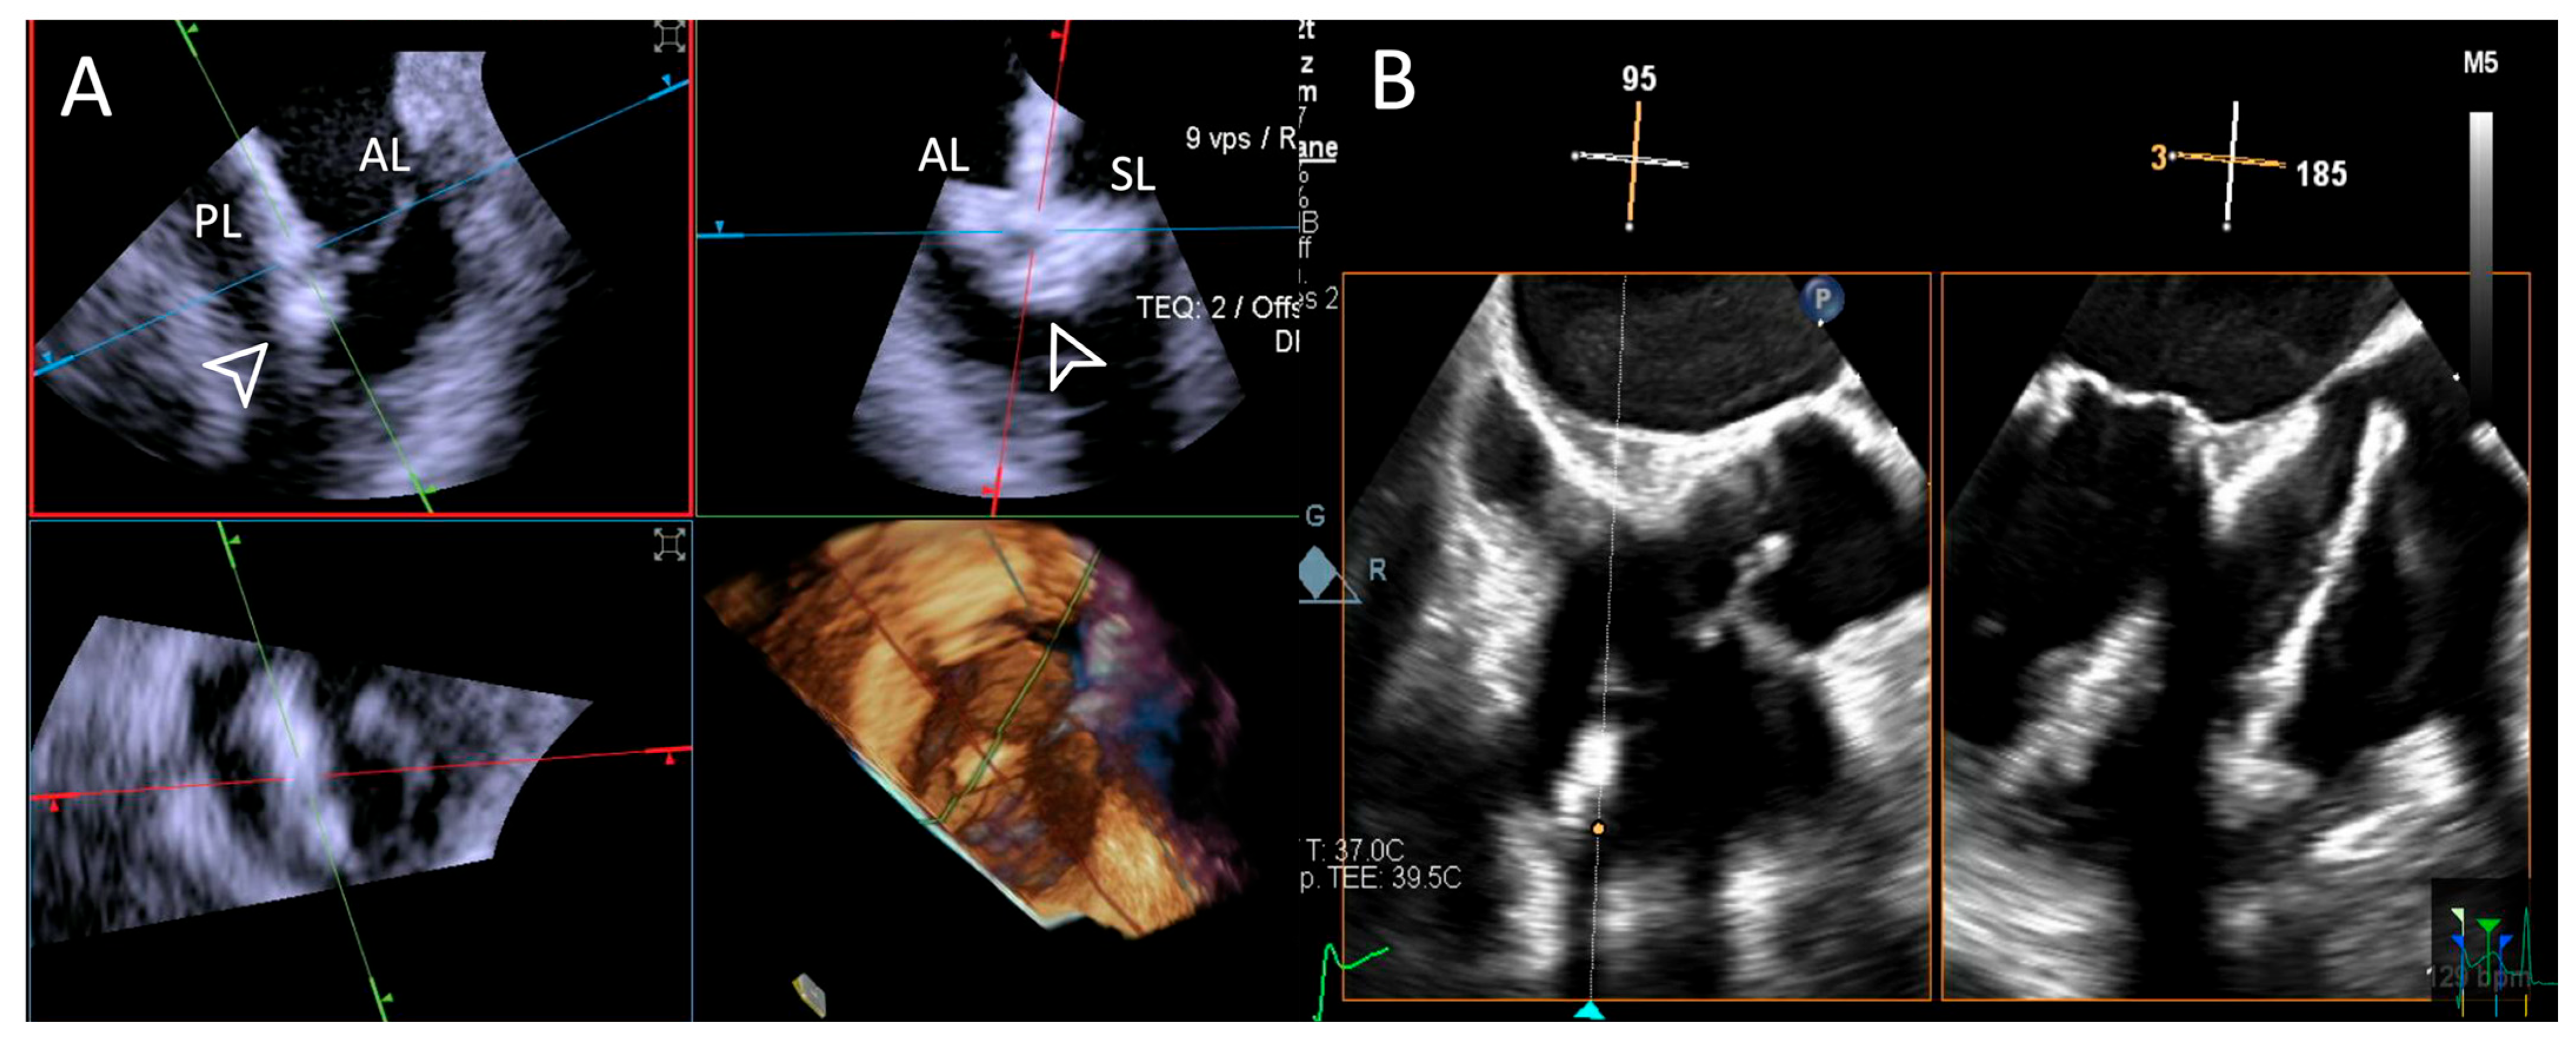

- Step number 5: clocking.

- -

- Step number 6: grasping.

- Step number 7: leaflet insertion.